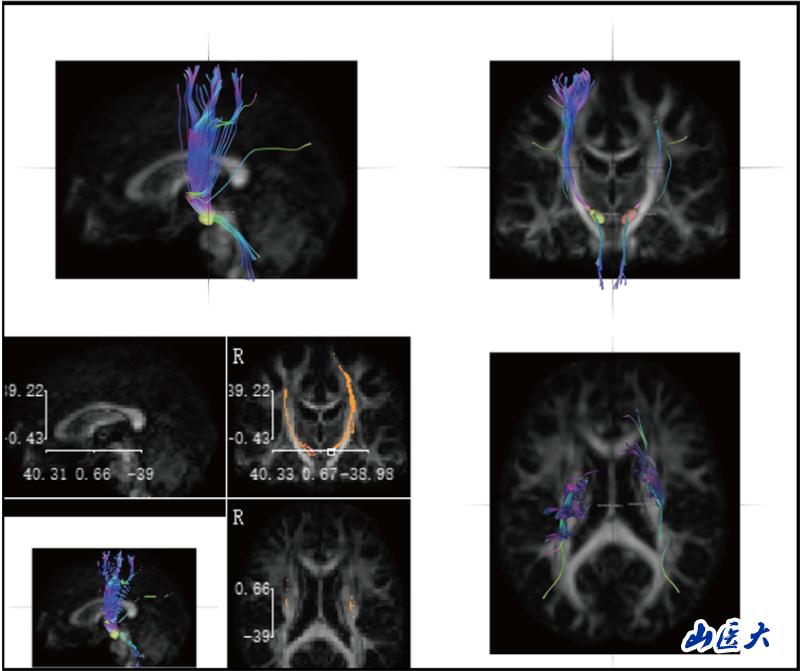

神经解剖学教学长期面临"结构隐匿性"与"空间复杂性"的双重挑战。传统的大体标本和平面模型难以展现纤维束、核团等微观结构的空间关系,易导致学生神经解剖结构认知困难。研究团队针对这一痛点,创造性引入前沿神经影像技术—DSI Studio纤维束成像系统。该技术通过对扩散磁共振成像(dMRI)数据分析,实现纤维路径智能追踪、三维动态重建及多维度交互可视化,构建起"影像解剖-病理对照-临床关联"的一体化数字教学体系。

研究团队创新性构建"理论-操作-临床"三阶整合教学模式,基于DSI Studio纤维束成像技术开展教学实践。选取38名低年级医学生为对象,通过整合人类连接组计划(HCP)标准脑数据库、帕金森病进展标志物计划(PPMI)及临床脑出血病例影像数据,建立"正常-病理"双模态教学资源库。此教学实践改革,不仅提升了学生神经解剖结构的空间理解力,并培养了学生从解剖结构认知到功能损伤解析的临床思维能力。